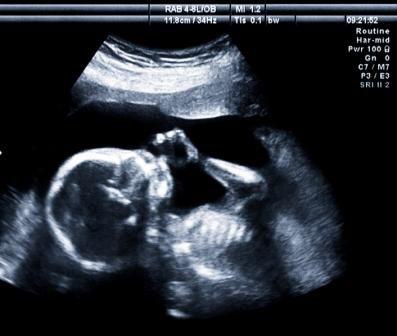

Cerebral palsy is a group of disorders traceable to a number of different causes. To determine the specific cause of cerebral palsy in an individual child, doctors must consider the prenatal history, the circumstances surrounding the labor and delivery, the specific symptoms experienced by the child, and the onset of the disorder. Common causes include intrauterine infection, perinatal infection, hypoxic ischemic encephalopathy and some genetic abnormalities.

While many cases of cerebral palsy are caused by incidents during pregnancy or birth or the immediate neonatal period after delivery, a smaller percentage of cases are acquired remote from birth.